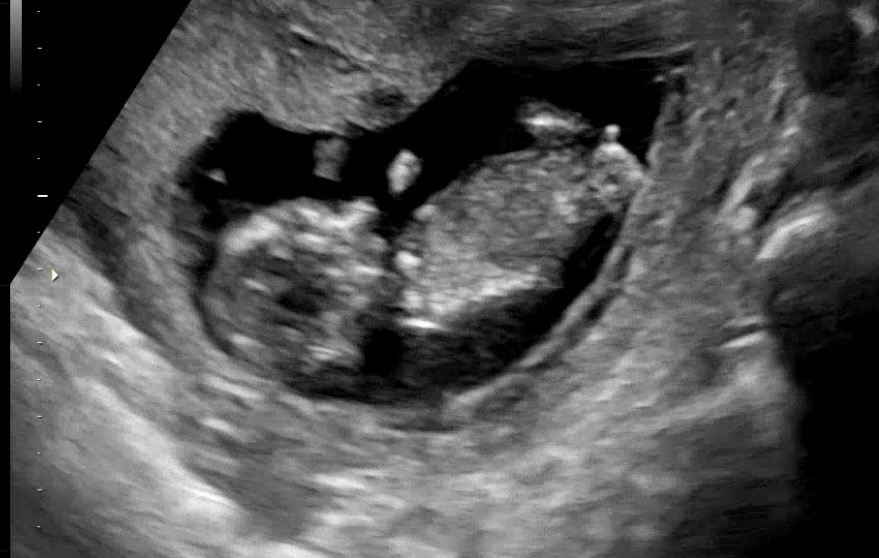

12주 2일차 각도법 질문드립니당

완벽한 옆모습은 아니지만 질문드려봅니다!

아들같아요!